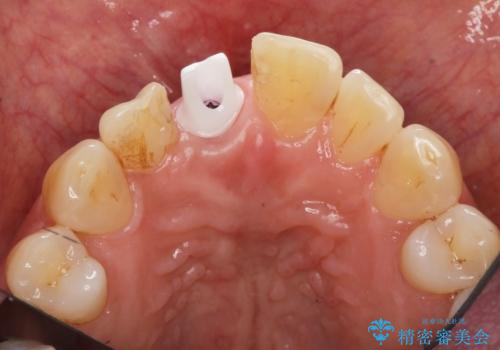

前歯 インプラントによる欠損補綴

- 50万円(ストローマンインプラント・骨造成・ジルコニアカスタムアバットメント・ジルコニアクラウン)費用は治療当時の料金となります

前歯のインプラント治療は適切に行えば、ブリッジのように隣の歯を削らずに審美的で機能的な状態に仕上げることが可能です。

インプラント周囲に十分な骨や歯ぐきの厚みの整備を行うことで、審美的なインプラントの仕上がりを達成することができます。